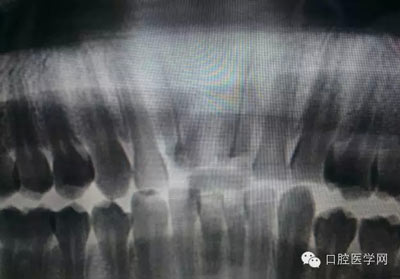

根管再治療是我們比較頭疼的,尤其是那些冠修復過的,我們有很多的麻煩需要去溝通,比如可能導致的側(cè)穿、可能沒有看到的腐質(zhì)、可能導致的崩瓷,或者是后期可能出現(xiàn)冠折......這些需要我們和患者好好的溝通。全瓷冠還好些,金屬冠根測的時候很是麻煩,總之我們做修復的時候不要單純的追求速度,追求效益,適當?shù)淖⒁庀挛覀兊幕A(chǔ)治療和設(shè)計。

這是一例外院樹脂修復后十個月出現(xiàn)牙髓炎癥狀的患者。遇到這樣子的患者大家會怎么做,證明選擇,還有就是可做可不做治療的如何去平衡。